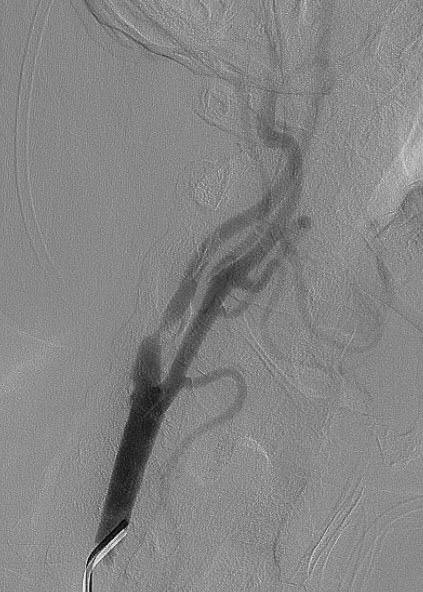

62-летний пациент жаловался на частые головные боли, головокружение и появление «мушек» перед глазами. Врачи провели ряд обследований и выявили критическое сужение (на 90%) правой внутренней сонной артерии. Было принято решение в кратчайшие сроки провести операции по установке стента для восстановления нормального кровотока.

После успешного лечения и контрольного обследования не было выявлено никаких нарушений кровообращения. Пациента выписали в удовлетворительном состоянии.